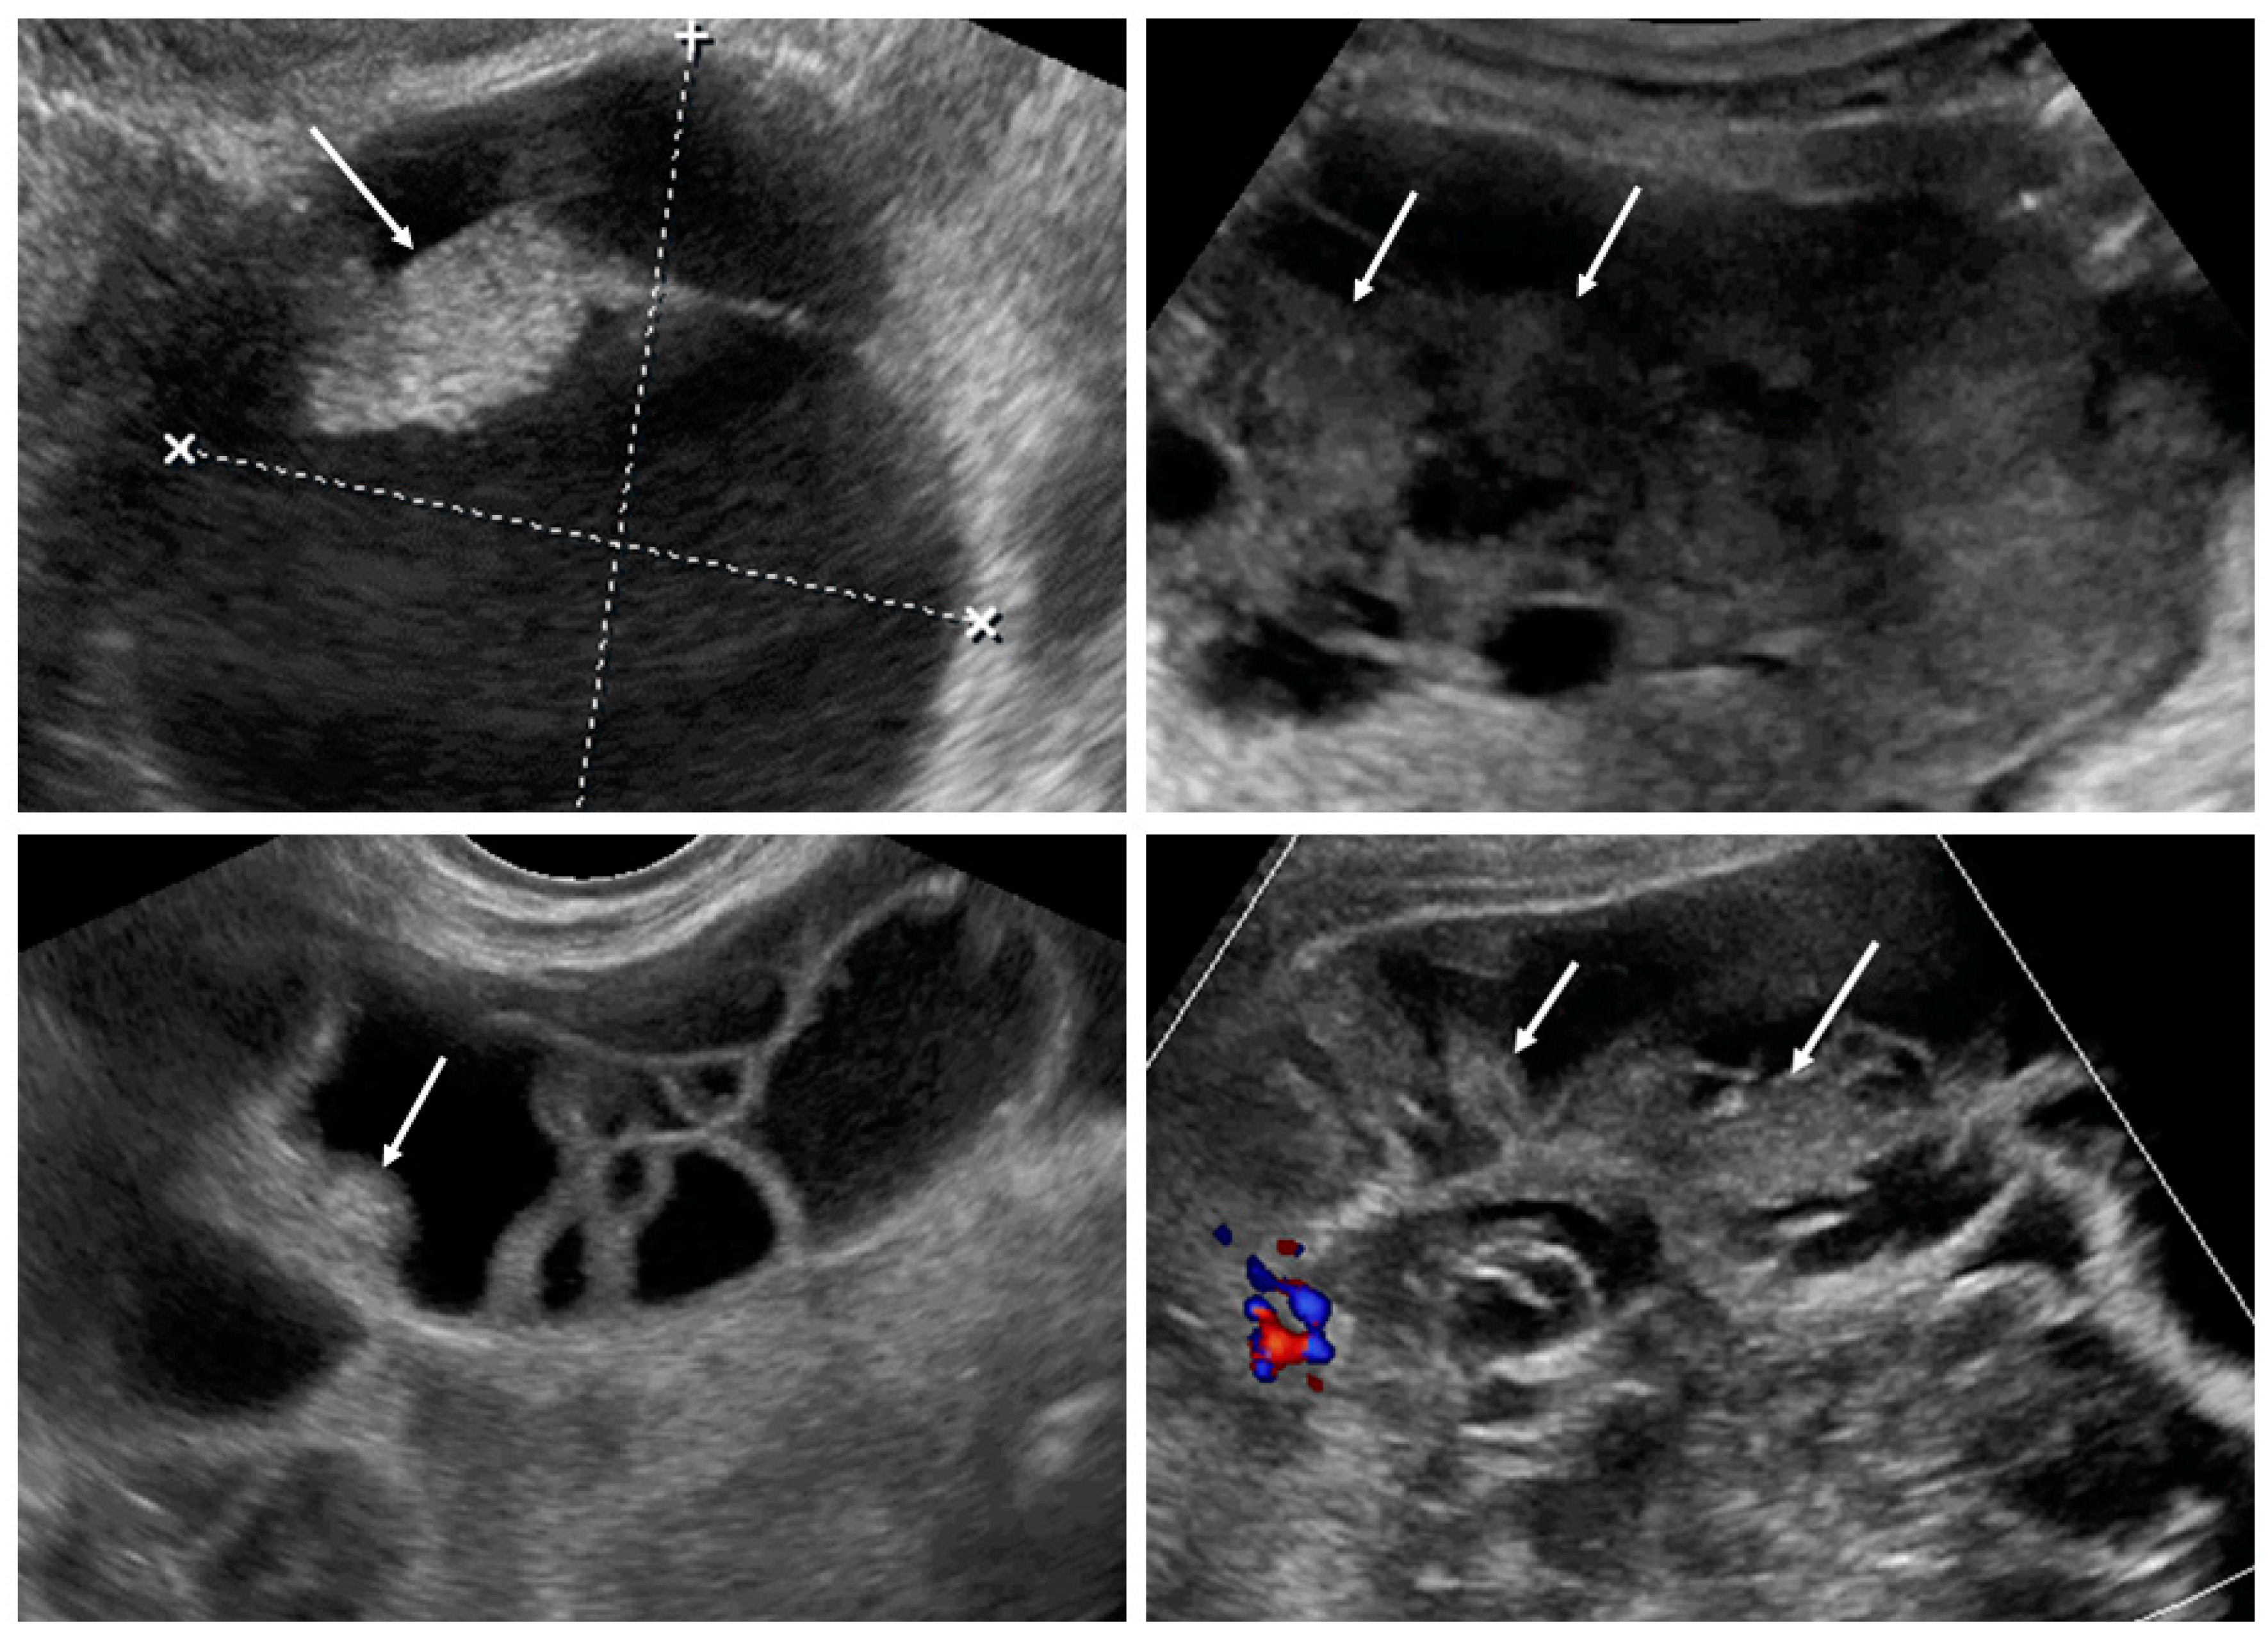

Figure 4.

Solid papillary projections (arrows) growing from the septa and inner wall. White dotted lines are measurements of the tumor.

After the collection of cases for the study was closed, a new observation was noted (by M.S.) when analyzing the videoclips of ovarian mCRC in detail. A tree-like sign was detected in multilocular-solid tumors, with parallel, closely-localized, septa (“trunk”) later branching in different directions (“branches”), forming an image resembling a tree (Figure 5, Video S3). Interestingly, the tree-like sign was not detected in any of matched controls with primary OC.

Figure 5.

Tree-like sign in a multilocular-solid tumor. White arrows indicate the “tree trunk”; yellow arrows indicate “tree branches”.